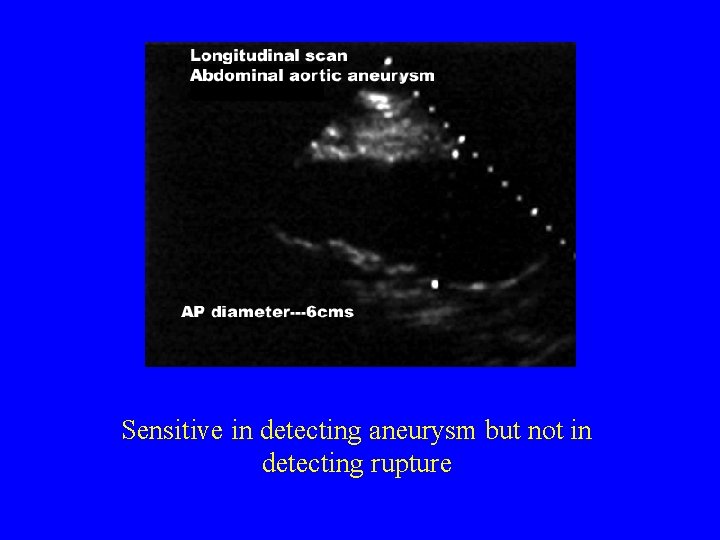

Diagnosis Imaging • Plain Films – Enlarged outline of calcified aortic wall • A retrospective review showed that 65% of x-rays form RAAA had calcified aortic wall – Loss of psoas shadow • Abdominal U/S – Sensitive in detecting aneurysm but not in detecting rupture • Abdominal CT – Most accurate method – See presence of retroperitoneal blood (77% sensitive and 100% specific)

Sensitive in detecting aneurysm but not in detecting rupture